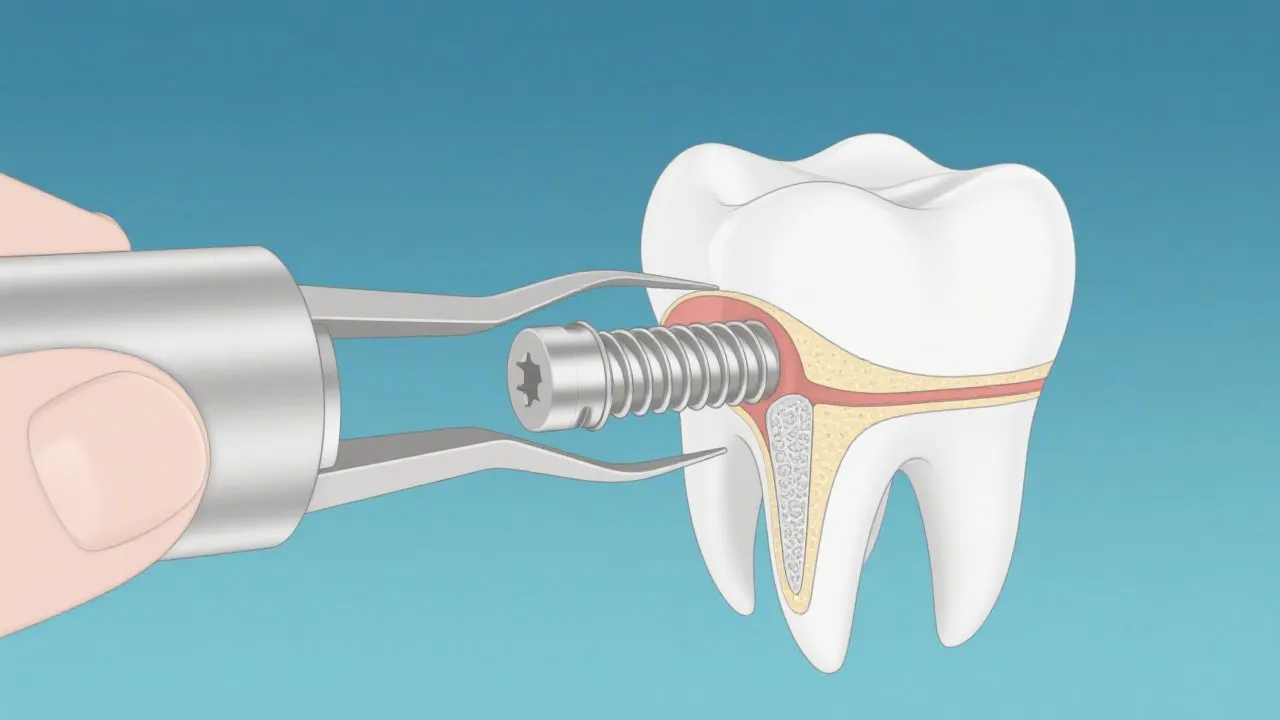

Dental implants have become a cornerstone of modern dentistry, especially when deemed medically necessary. They are titanium posts that replace missing tooth roots, providing a base for crowns that mimic natural teeth in both appearance and function. Recognized for their stability and durability, dental implants have revolutionized tooth replacement solutions, especially in cases where traditional dentures may fall short. The materials used for dental implants, usually titanium or titanium alloys, exhibit excellent biocompatibility, which allows the bone to grow around the implant—an essential part of the treatment's success.

4. **Surgical Procedure and Recovery** - The implant procedure itself followed by a recovery phase, ensuring the implant integrates with the jawbone successfully. This integration process, known as osseointegration, can take several months and is critical for the long-term success of the implant.